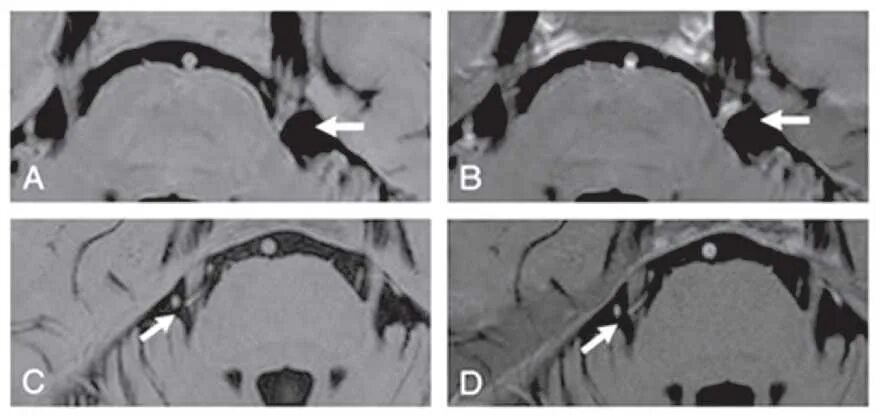

Нейроваскулярный конфликт нерва